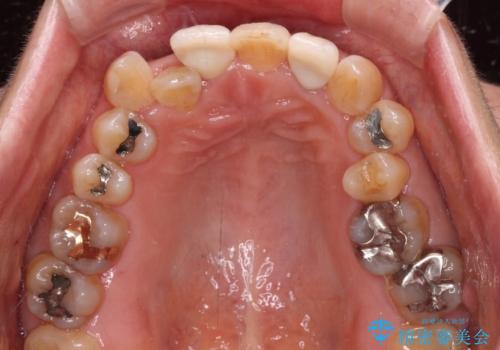

- 20年以上前に神経を取り除いた前歯の変色が気になるとのことで来院された患者様です。

レントゲン写真より、歯根の炎症が認められなかったため、ファイバーコアによる土台築製後、オールセラミッククラウンにて補綴することとしました。

また、真ん中の前歯はコンポジットレジンによる修復跡が目立っており、合わせてオールセラミッククラウンにて治療することとしました。

歯に独特の縞模様があり、さらに特徴的な色合いであったため、コンポジットレジンによる修復では対応が困難でした。

オールセラミッククラウンは周囲の歯よりもやや白く製作し手降りますが、今後はご自身でホワイトニングをして明るい色調で整えるとのことでした。